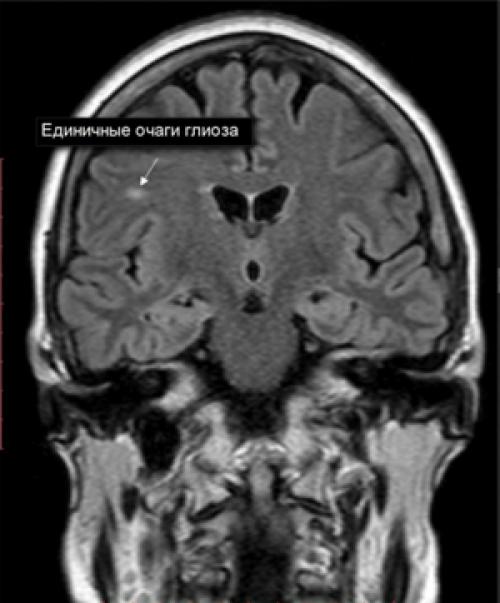

Единичные очаги глиоза

Для очагового глиоза характерны единичные четко ограниченные островки в белом веществе, размер и расположение которых определяется причинами гибели нейронов. Встречаются у лиц любого возраста и, может быть, как проявлением естественных возрастных дегенеративных процессов в тканях мозга, ишемии церебральных структур , локального воспалительного процесса, хронической гипертонии , процесса демиелинизации , так и следствием травм в родах у младенцев.

Единичный очаг глиоза

Обычно единичные (ограниченные очаги) глиоза головного мозга являются случайной находкой на КТ/МРТ, поскольку в большинстве случаев они клинически не проявляются и дискомфорта не приносят, за исключением их локализации в лобной доле, где расположены центры, ассоциирующиеся с чувствами и ощущениями, что может проявляться появлением галлюцинаций . Единичный глиоз головного мозга не склонен к разрастанию.